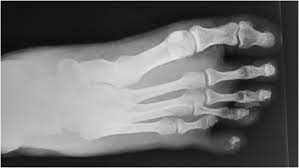

A degloving injury is defined as a type of injury in which the skin is degloved or removed from an area of the body leaving behind only the muscle or bone. We report a case of degloving injury of the leg and the foot in a passenger of a motor vehicle and suggesting a biomechanics of the injury. Road racing in the UK and in Ireland is an exciting spectacle to witness but behind the scene a different of spectacle unfolds.